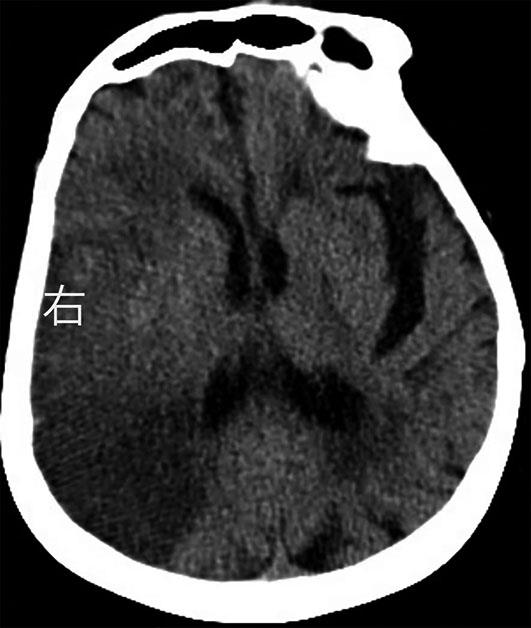

• 挽救性支架植入对取栓困难的脑动脉栓塞开通效果

摘要:目的 探究急性脑栓塞取栓失败和神经介入术中发生医源性脑动脉栓塞后补救性支架植入术的开通效果。方法 回顾性分析2020年1月至2021年11月上海交通大学医学院附属第九人民医院6例脑栓塞取栓失败和4例医源性颅内中远端动脉栓塞、接受补救性支架植入术的患者临床信息,总结患者术后血管开通情况、术后24 h 支架内血流通畅情况、出血转化和预后等情况。结果 6例急性脑栓塞取栓失败,补救性支架植入后闭塞血管全部开通(modified thrombosis in cerebral infarction score,mTICI 2b~3),术后3例出血转化(1例PH2型,2例HI2型),术后24 h支架内血流通畅5例(83%),1例未行血管造影复查;3例患者住院期间死亡。4例医源性中远端动脉闭塞中,1例为原发病为椎基底动脉高度狭窄,支架置入术中发生右侧小脑前下动脉闭塞,补救性支架置入后完全开通,术后24 h复查所有支架通畅,无脑出血,3个月预后良好,改良Rankin量表(modified Rankin score,mRS)评分1分;3例原发病为大脑中动脉栓塞,取栓术中出现同侧大脑前动脉分支闭塞,补救性支架植入后完全开通,其中1例术后24 h头颅计算机体层血管成像(computed tomography angiography,CTA)可见支架通畅,合并片状出血转化(HI2型),2例因为病重未行血管复查。结论 补救性支架植入可以快速开通取栓失败以及医源性中远端动脉的栓塞,但是疗效和安全性需进一步研究。